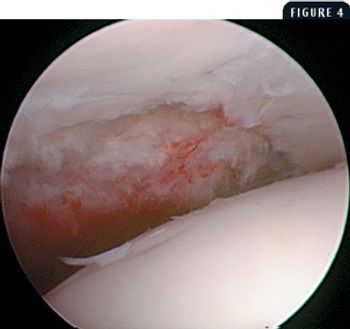

A 10-month-old 136-lb (62-kg) female Irish wolfhound was presented for evaluation of right forelimb lameness of four months' duration.